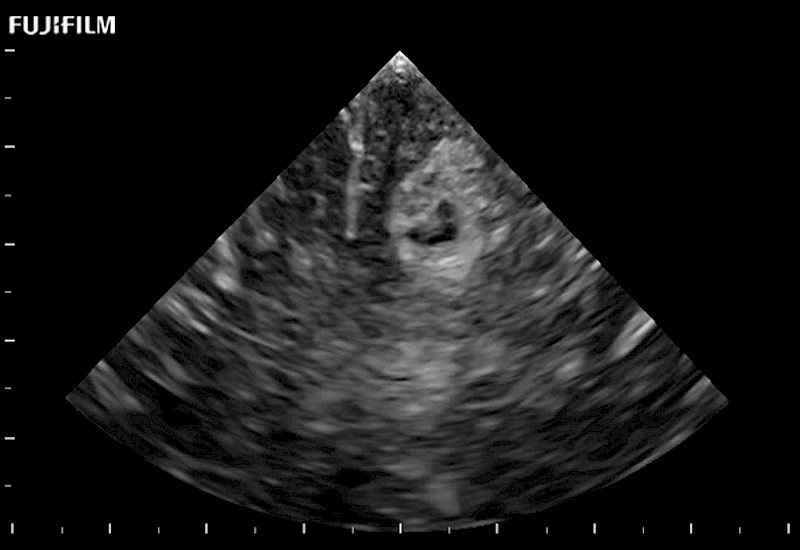

Tight curved (12mm) array transducer that is ideal for scanning during cranial guidance procedures.

The world's only phased array burr-hole transducer that is ideal for scanning during burr-hole guidance procedures.

Smaller footprint (20mm) curved array transducer that is ideal for scanning during cranial guidance procedures.